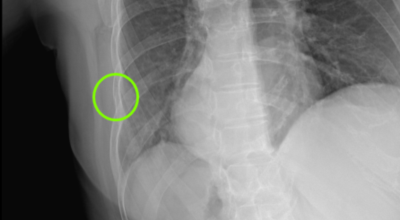

일반인이 근육의 통증과 금이 간 경우의 차이는 거의 판별하기 힘들게 됩니다. 갈비뼈라고 하는 부분이 눈에 보이도록 붓는 것도 아니고, 멍이 들어서 아픈것도 아니기 때문이예요. 가장 정확하게 판별하는 방법은 엑스레이를 찍는 방법이예요.